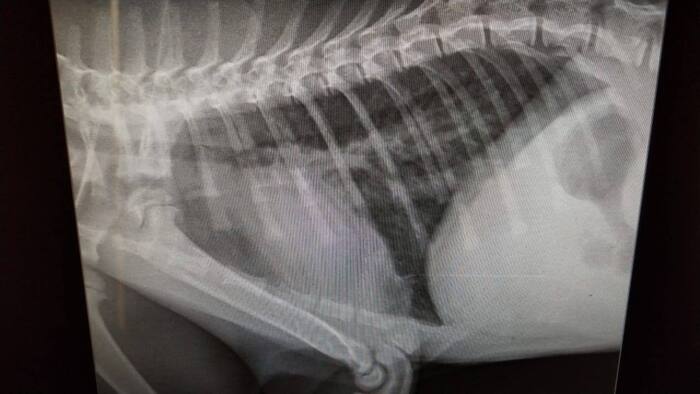

Всем привет. Хозяин (слава летающему чайнику) вышел на звяь и отнес котенка в Леноблвет на анализы. Он, кстати, взял его на Юле от домашней кошки. Денег нет, платим мы. Котенок живой. Температуру держит, активнее, чем вчера. Как придет кровь, будет ясно, какие инфузии можно будет делать.